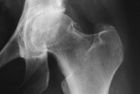

When you are suffering from hip arthritis, it can be very difficult to imagine what the cause of the problem really looks like. To give you an impression, we compiled a series of images found on the next page. The X-ray image is seen on the right, and the associated femoral head on the left. When you look at the pictures of the bones on the left, it becomes immediately clear that such joints would cause massive pain, and that an artificial hip replacement would be the only good solution.

We do not have images from less damaged joints to show because, in such cases, we have already made every effort and preserved the natural joint.